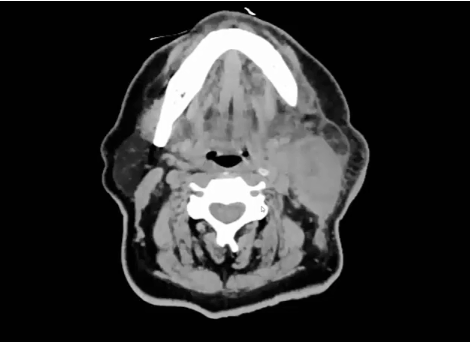

08/10/2021 - Dr. Kenneth Hu - Radiation Oncology - US Head & Neck